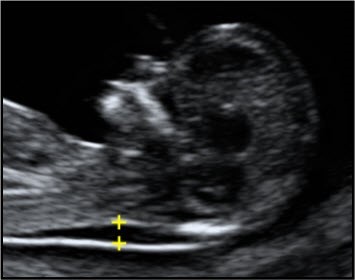

Criteria for measurement of the fetal nuchal translucency (NT) measurement

A midline sagittal section of the fetus should be obtained. The fetus should be horizontal on the screen, either supine or prone.

Care must be taken to distinguish between fetal skin and amnion. The fetus should be in a neutral position.

The image should be magnified, such that only the fetal head and upper thorax occupy the whole screen. In magnifying the image (pre- or post-zoom) it is important to turn down the gain.

The widest part of the translucency must always be measured. Measurements should be taken with the horizontal lines of the callipers placed ON the lines that define the NT thickness.

During the scan more than one measurement must be taken and the maximum one which meets all the criteria should be recorded. Two images of this measured NT should be retained, one for the patient record, one for audit purposes.